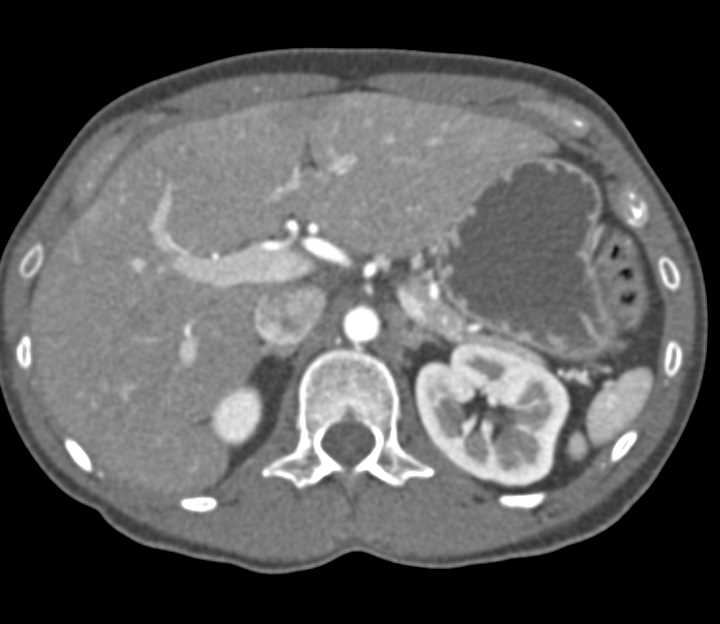

Hepatocellular Carcinoma (Hepatoma) Infiltrates Liver and Extends into Inferior Vena Cava (IVC) and Right Atrium